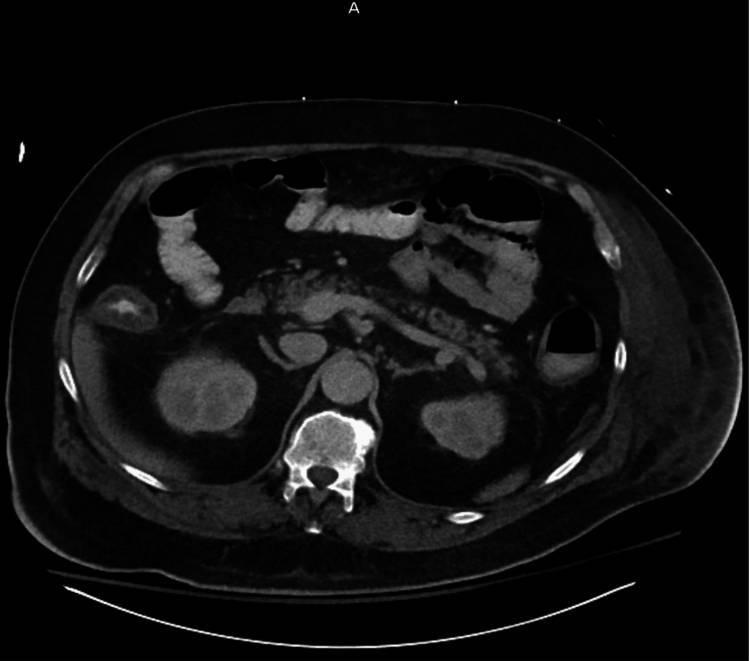

入院实验室数据如(表1)所示。腹部和骨盆的计算机断层扫描(CT)扫描和静脉注射(IV)造影显示结肠梗阻,膨胀的升结肠直径接近11cm,存在周围PI(图1)。横结肠也因积气而扩张,而降结肠扩张较少;在降结肠中部存在一个过渡点,没有观察到任何肿胀(图2)。

图2 腹部和骨盆的CT扫描显示,过渡点位于降结肠中部(箭头)